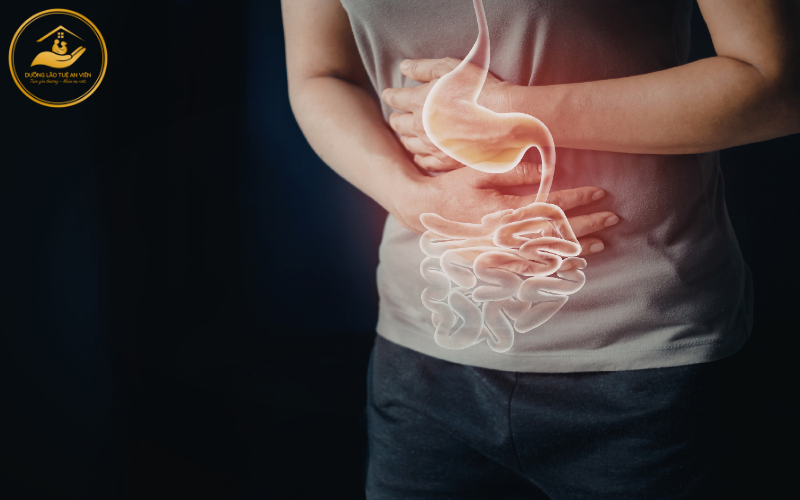

1.3 Hệ tiêu hóa hấp thu kém làm giảm hiệu quả phục hồi

Ở người cao tuổi, hệ tiêu hóa hoạt động kém hiệu quả hơn:

-

Giảm tiết men tiêu hóa

-

Hấp thu dưỡng chất chậm

-

Dễ chán ăn, ăn ít

Nếu chế độ dinh dưỡng không được thiết kế phù hợp, cơ thể sẽ không đủ năng lượng để đáp ứng nhu cầu phục hồi. Điều này làm suy giảm nghiêm trọng vai trò của dinh dưỡng trong quá trình phục hồi chức năng, khiến các bài tập vật lý trị liệu không đạt hiệu quả như mong muốn.